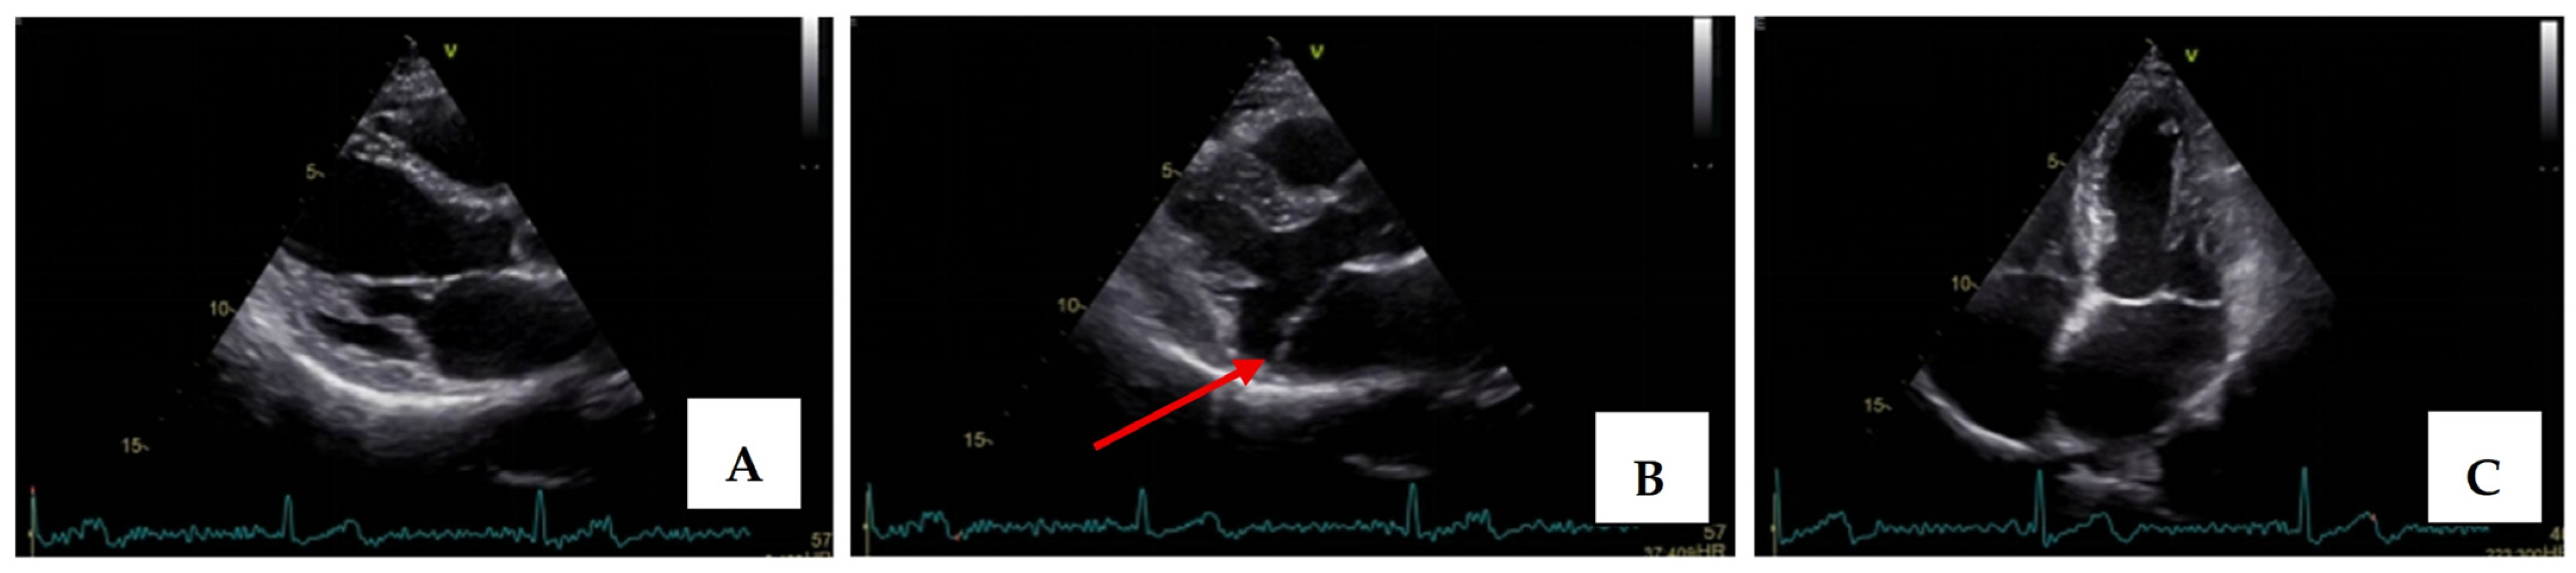

Transthoracic echocardiography revealed myxomatous degeneration of the mitral valve with bileaflet redundancy, increased leaflet length and thickness, and prolapse of both leaflets. Notably, a mitral annular disjunction (MAD) measuring 10 mm was observed in the parasternal long-axis view at end-systole (Figure 2A–C). Additionally, systolic “curling motion” of the posterolateral wall of the left ventricle was present, and the Pickelhaube sign was documented (Figure 3).

Figure 2.

Mitral valve prolapse with MAD on transthoracic echocardiography (TTE). (A)—TTE parasternal long-axis view in end-diastole displaying excessive leaflet length and thickness, (B)—TTE parasternal long-axis view in end-systole displaying mitral annular disjunction-MAD of 10 mm length (red arrow), and (C)—apical 4-chamber view displaying a displacement of both leaflets > 2 mm above the plane of the annulus.